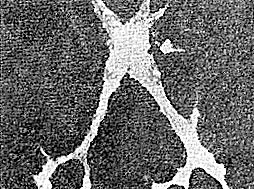

Причины этого заболевания, известного под названием подострый склерозирующий панэнцефалит (сокращенно – ПСПЭ), долгое время оставались неизвестными. Но вот с середины 1960-х годов исследованием ПСПЭ начинают заниматься вирусологи. А побудило их к этому обнаружение Дж. Даусоном в клетках головного мозга погибших от ПСПЭ детей определенных образований (рис. 10). Данная находка заинтересовала ученого потому, что подобного рода структуры, называемые тельцами включений, нередко образуются в клетках разнообразных тканей при вирусных заболеваниях: оспе, бешенстве, герпесе, кори, эпидемическом конъюнктивите, гриппе, аденовирусной инфекции и др. ![]() Рис. 10. Тельца включений (показаны стрелками) в культуре клеток мозга, полученных от пациента, страдавшего подострым склерозирующим панэнцефалитом Тельца включений при перечисленных заболеваниях представляют собой скопления размножающихся вирусных частиц. Они достигают значительных размеров – от 0,2 до 25 мк [8] – и могут быть круглой, овальной, удлиненной или эллипсовидной формы. Их расположение в клетке неодинаково при различных заболеваниях. Так, например, при бешенстве и оспе тельца включений формируются в цитоплазме клеток, при герпесе и желтой лихорадке – в ядрах. Характер расположения, внешний вид, свойства (отношение к красителям) телец включений служат характерными признаками некоторых вирусных заболеваний, а большие размеры позволяют их легко обнаружить с помощью обычного светового микроскопа. К примеру, обнаружение телец включений играет важнейшую роль в лабораторной диагностике таких вирусных заболеваний, как бешенство и оспа. А теперь, читатель, ответьте на такой вопрос – что интересует врача, выслушавшего жалобы больного, в первую очередь? Да, безусловно, его анализ крови. Кровь, питающая клетки организма кислородом и снабжающая их всем необходимым для жизни, выводящая углекислоту и шлаки, постоянно присутствует во всех «уголках» нашего организма. И, несмотря на упорное стремление поддерживать свой состав на постоянном уровне, кровь, конечно же, быстрее всех других составляющих организма реагирует на происходящие сбои в его работе. А потому вирусологи прежде всего решили заглянуть в кровь больных ПСПЭ детей. Ведь если ПСПЭ – вирусное заболевание, то наверняка организм ответит образованием антител на вирус-возбудитель. Заглянули – и поразились: в крови больных ПСПЭ детей обнаруживались высокие титры противокоревых антител (титр – это наименьшее количество исследуемого материала, в котором еще определяется противовирусная активность антител). Для того чтобы оценить всю сенсационность этой находки, следует напомнить, что и у нас с вами, читатель, в крови присутствуют противокоревые антитела (ведь мы в большинстве своем переболели в детстве корью). И в нашем организме титр таких антител соответствует разведению сыворотки крови примерно 1:40. В крови же детей, страдающих ПСПЭ, титр противокоревых антител нередко достигает 1:16 000! Этот факт не говорил, он кричал! Скрупулезное изучение клеток головного мозга погибших от ПСПЭ детей подтвердило наличие в них телец включений, как две капли воды похожих на включения, характерные для вируса кори. Исследователи пошли дальше. Из мозговой ткани больных приготовили сверхтонкие срезы, которые можно рассматривать не только в световой, но и в электронный микроскоп. Этот прибор позволил выявить внутри таких телец включений большие скопления кореподобных вирусных частиц. Наконец, последнее косвенное доказательство причастности вируса кори к этому фатальному заболеванию получили с помощью метода флуоресцирующих антител. Обычные (не сверхтонкие) срезы мозговой ткани погибших от ПСПЭ детей обрабатывают иммунными сыворотками, содержащими помеченные светящимся веществом антитела к различным вирусам. Свечение тканевых срезов будет наблюдаться только в том случае, если антитела свяжутся с вирусом, находящимся в ткани. Из схемы (рис. 11) легко понять, что антитела, не соответствующие данному вирусу, не смогут с ним связаться и потому при отмывании среза ткани будут с него смыты. Если же сыворотка с меткой содержит как раз те антитела, которые соответствуют находящемуся в клетке вирусу, то они легко свяжутся с ним и отмыванием их уже нельзя будет удалить с поверхности среза. В таком препарате мы и увидим на срезе участки свечения. ![]() Рис. 11. Схематическое изображение принципа метода флуоресцирующих антител: А – в реакции использованы антитела, соответствующие данному вирусу; обработанные препараты клеток светятся (реакция положительная); Б – в реакции использованы антитела, не соответствующие данному вирусу; при промывании такого препарата не связавшиеся с вирусом (антигеном) антитела удаляются, свечения не будет (реакция отрицательная) Срезы мозговой ткани больных ПСПЭ обрабатывали различными сыворотками со светящейся меткой. Пораженные мозговые клетки светились ярким изумрудным светом только в том случае, когда срезы обрабатывали противокоревой сывороткой (рис. 12). ![]() Рис. 12. Свечение клеток мозга больного подострым склерозирующим панэнцефалитом, обработанных противокоревой флуоресцирующей сывороткой Можно было только радоваться быстрому успеху исследователей. Казалось, до получения прямого доказательства коревой природы заболевания остается всего один шаг – нужно лишь выделить из пораженной мозговой ткани коревой вирус. Но именно здесь ученых подстерегали большие трудности. И шаг этот растянулся на годы напряженнейших поисков в различных лабораториях мира. Не буду нагружать читателя подробностями различных подходов к решению данной проблемы. Отмечу лишь, что настоящий успех в поиске выпал на долю группы исследователей из Национального института неврологических заболеваний в городе Бетесде (США). Коллектив американских вирусологов, руководимый Луизой Хорта-Барбозой, применил так называемый метод смешанных культур клеток: в матрасах вырастили однослойную культуру раковых клеток человека HeLa [9] и на этот «ковер» поместили клетки мозговой ткани больного ребенка, предварительно обработанные трипсином. Прошло несколько дней, и клетки HeLa начали сморщиваться, отъединяться друг от друга, а затем и вовсе распадаться. В чем тут было дело? Оказалось, в вирусе кори! |